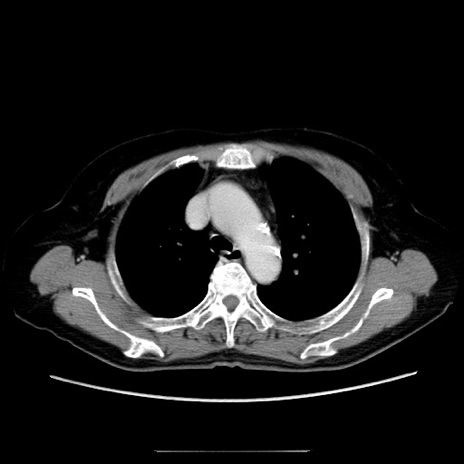

症例5(横断像)

【症例】70歳代女性

【主訴】お腹が張る

【現病歴】1週間くらい前から腹部膨満の自覚あり。昨日夜から増悪したため、本日救急外来受診。

【身体所見】意識清明、BT 36.5℃、BP 165/106mmHg、HR 80bpm、SpO2 98%、腹部:膨満、軟、自発痛・圧痛なし、触診にて不快感あり、腸蠕動音:減弱

【データ】WBC 12600、CRP 1.04